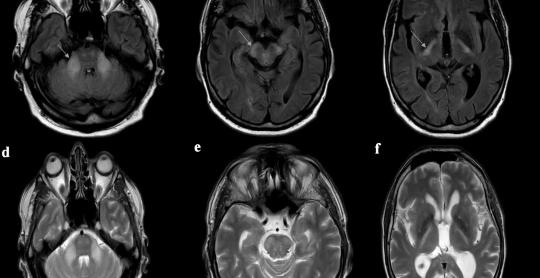

Journal of Neurology Research

Vol. 16, No. 1, Mar 2026, pages 1-8

By Adamantios Katerelos et al.